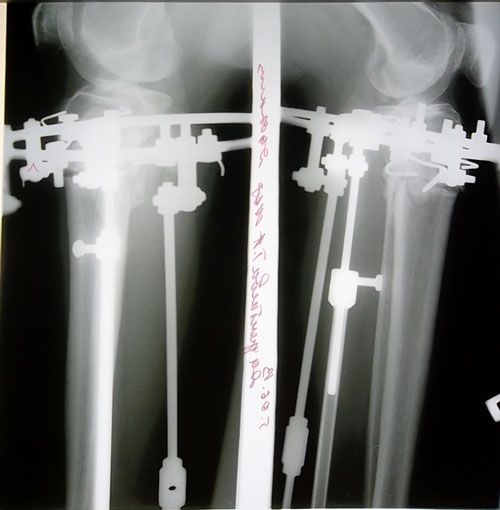

Дата операции 11.01.2013г.

Дата снятия аппаратов 01.07.2013г.

Срок лечения 169 дней.